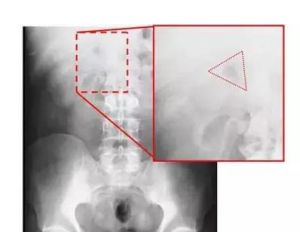

結構 原理 價值 注意事項腹部空腔臟器因炎症或外傷等因素導致破裂穿孔後,立位狀態下,氣體積聚於隔肌下方,叩診肝濁音界縮小或消失,X線可見緊貼膈下新月形游離氣體影徵象。